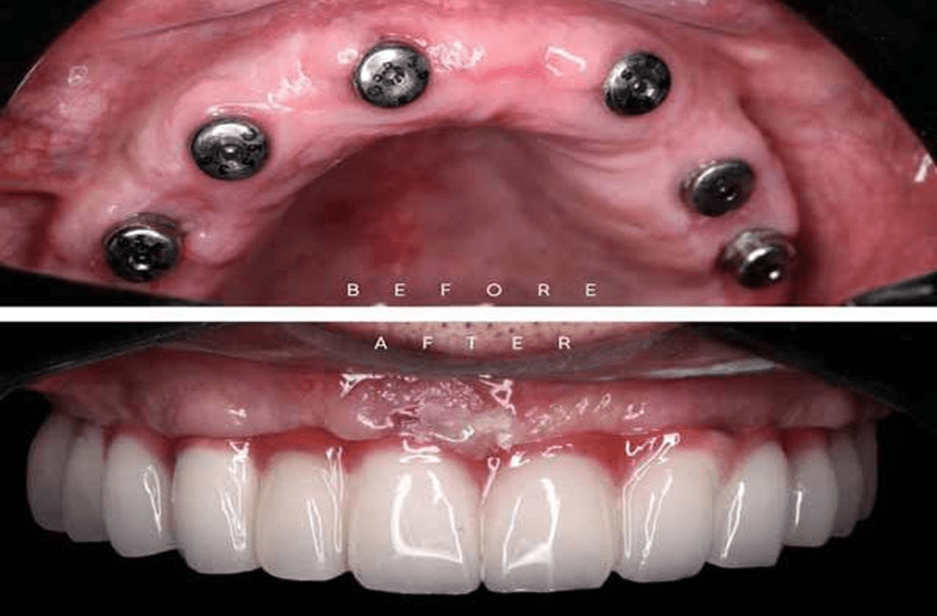

- پس از اینکه استخوانهای فرد آماده شد، جراحی ایمپلنت کامل صورت میگیرد. متخصص ایمپلنت، پایههای ایمپلنت را داخل استخوان تعبیه میکند.

- پس از اینکه پایههای ایمپلنت داخل استخوان قرار گرفتند، فرد باید دوره نقاهت را پشت سر بگذارد. در این دوره، شاهد جوش خوردن پایهها به استخوان خواهیم بود.

- پس از جوش خوردن پایههای ایمپلنت، نوبت به قالبگیری و روکش موقت میرسد. قالبها به لابراتور فرستاده میشوند تا پروسه آماده سازی روکشهای سفارشی شما انجام گیرد.

- مرحله نهایی را میتوان قرار گرفتن روکش دائمی دانست. در این مرحله، روکشها توسط لابراتور آماده شدهاند و متخصص آنها را روی پایه ایمپلنت نصب میکند و پروسه ایمپلنت کامل دهانی به پایان میرسد.